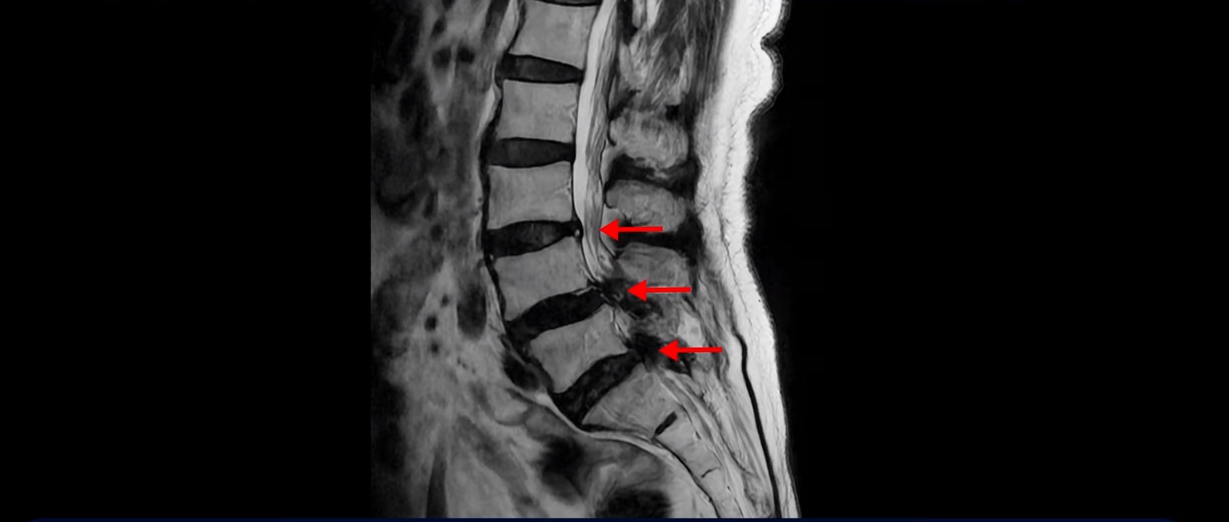

그런데도 아직도 많은 분들이 근육의 중요성을 모르고 신경치료만 하고 있습니다. 하지만 근육과 신경은 떼놓고 생각할 수가 없습니다. 근육이 나빠지면 신경 눌림이 심해져서 협착증 증상이 더 악화되고, 또 신경이 눌리면 근육도 더 빨리 나빠집니다. 반대로 근육이 좋아지면 신경 눌림이 줄어들고 협착증이 좋아집니다. 신경이 눌린다고 하니까 신경 눌림을 풀어주는 수술만 생각을 하시는 분들이 많은데 근육이 좋아져서 허리를 잘 지지해주면 신경이 덜 눌립니다. 이 환자분도 근육이 얼마나 안 좋은 지는 이분 척추가 얼마나 휘어있는 지만 봐도 알 수 있습니다. 보시다시피 근육들이 척추를 잘 지지하지 못하니까 척추가 심하게 휘어있습니다.